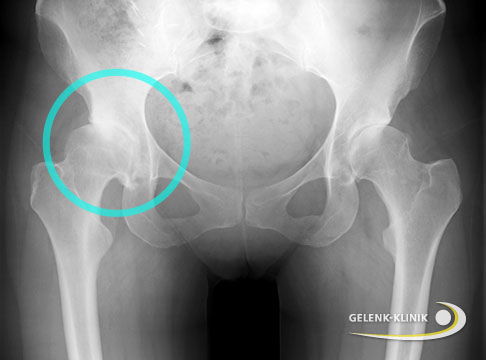

Bildgebende Untersuchung einer Hüftdysplasie bei Jugendlichen und Erwachsenen: Röntgen

Zur Abklärung eines Verdachts auf Hüftdysplasie bei jugendlichen oder erwachsenen Patienten fertigt der behandelnde Orthopäde röntgenologische Übersichtsaufnahmen des Beckens an. Er bewertet bei den Röntgenaufnahmen zwei Fragestellungen:

- Überdacht die Hüftpfanne den Hüftkopf ausreichend?

- Wie steht der Oberschenkelkopf im Gelenk?

Kann man eine Hüftdysplasie auf dem Röntgenbild erkennen?

Vor allem bei älteren Kindern und Erwachsenen kann man die Hüftdysplasie meist sehr gut im Röntgenbild erkennen. Die Hüftpfanne ist zu wenig ausgebildet und der Hüftkopf steht nicht zentriert in der Mitte der Pfanne. Häufig verschiebt sich der Hüftkopf auch nach außen oben. Der Schweregrad der Dysplasie kann zudem im Röntgenbild mit verschiedenen Winkeln bestimmt werden. Bei Säuglingen ist die Verknöcherung noch wenig fortgeschritten, deshalb ist bei ihnen zum Erkennen der Hüftdysplasie der Ultraschall überlegen.